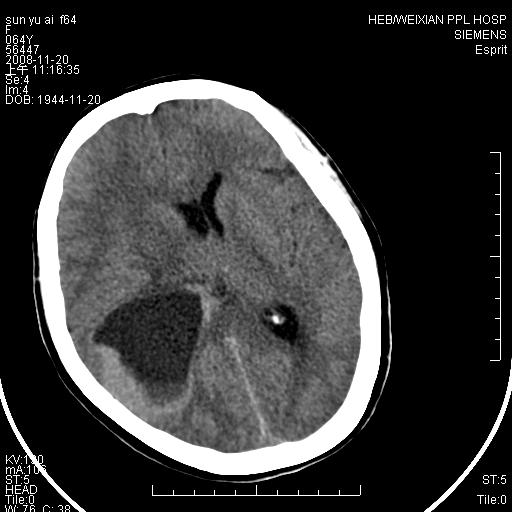

标题: CT16778:F64Y,颅内囊性占位 [打印本页]

影像表现:侧脑室三角区附近可见以形态不规则的囊实性肿块,其中以囊性成分为主,实性成分为辅,边缘清晰,未见水肿,轻度占位效应,脉络丛钙化向内上移位,右侧脑室轻度扩大(也许体位所致),

影像诊断:1室管膜瘤

2胆脂瘤 建议增强吧

1、右侧大脑半球囊实性占位病变,以囊性变为主,实性部分位于病变外后侧,周围无明显水肿,占位征象明显。

2、多考虑胶质瘤可能性大。

右颞顶叶囊实性占位,有壁结节。考虑间变性胶质瘤可能性大,建议增强进一步检查。

囊实性占位,实性部分为等密度或稍高密度,无明显水肿征考虑 -----脑膜瘤或室管膜瘤.其他待排,建议mri 增强检查